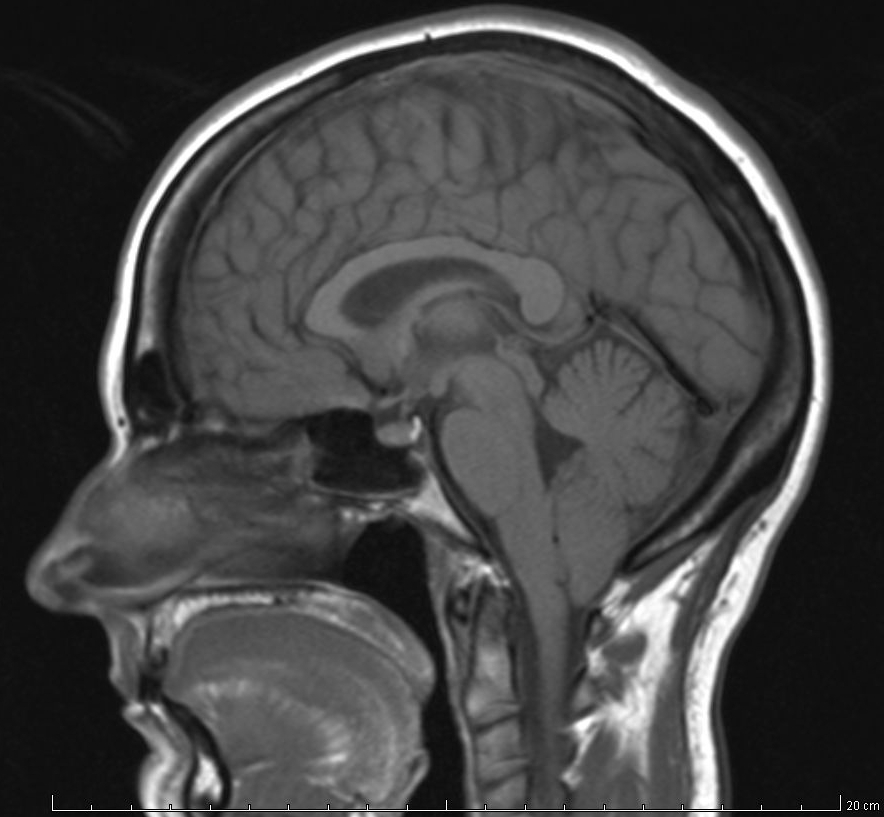

Chiari I Malformation

isolated low lying cerebellar tonsils

usu don’t need surgery

occasionally has a syrinx